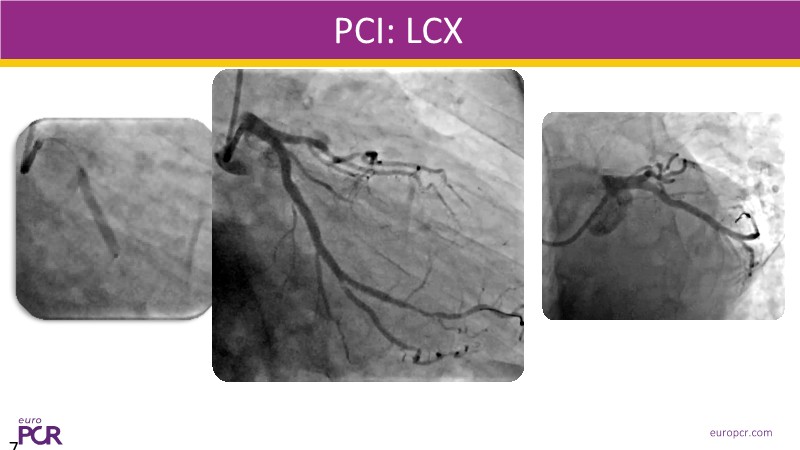

Watch this EuroPCR 2025 session to see how ELCA can make the difference in two challenging cases: a severely calcified, undilatable lesion, and an uncrossable one. Learn how pre- and peri-procedural imaging (CT, IVUS, OCT) supports tailored decision-making, and how ELCA enables safe and effective lesion preparation—through surface cracking and tissue softening—for optimal stent expansion. The second case highlights its value in precision wiring, especially in CTO-CHIP centres. Get practical tips to safely integrate laser into your complex PCI strategy.